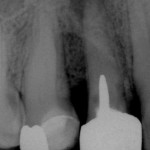

Endodonzia, conservativa e ritrattamenti, tre video arricchiscono il nostro sito

Lesione endo perio Perforazioni iatrogene di un elemento dentario possono chiaramente avere come conseguenza la formazione di lesioni endo-parodontali, che spesso compromettono la prognosi di...